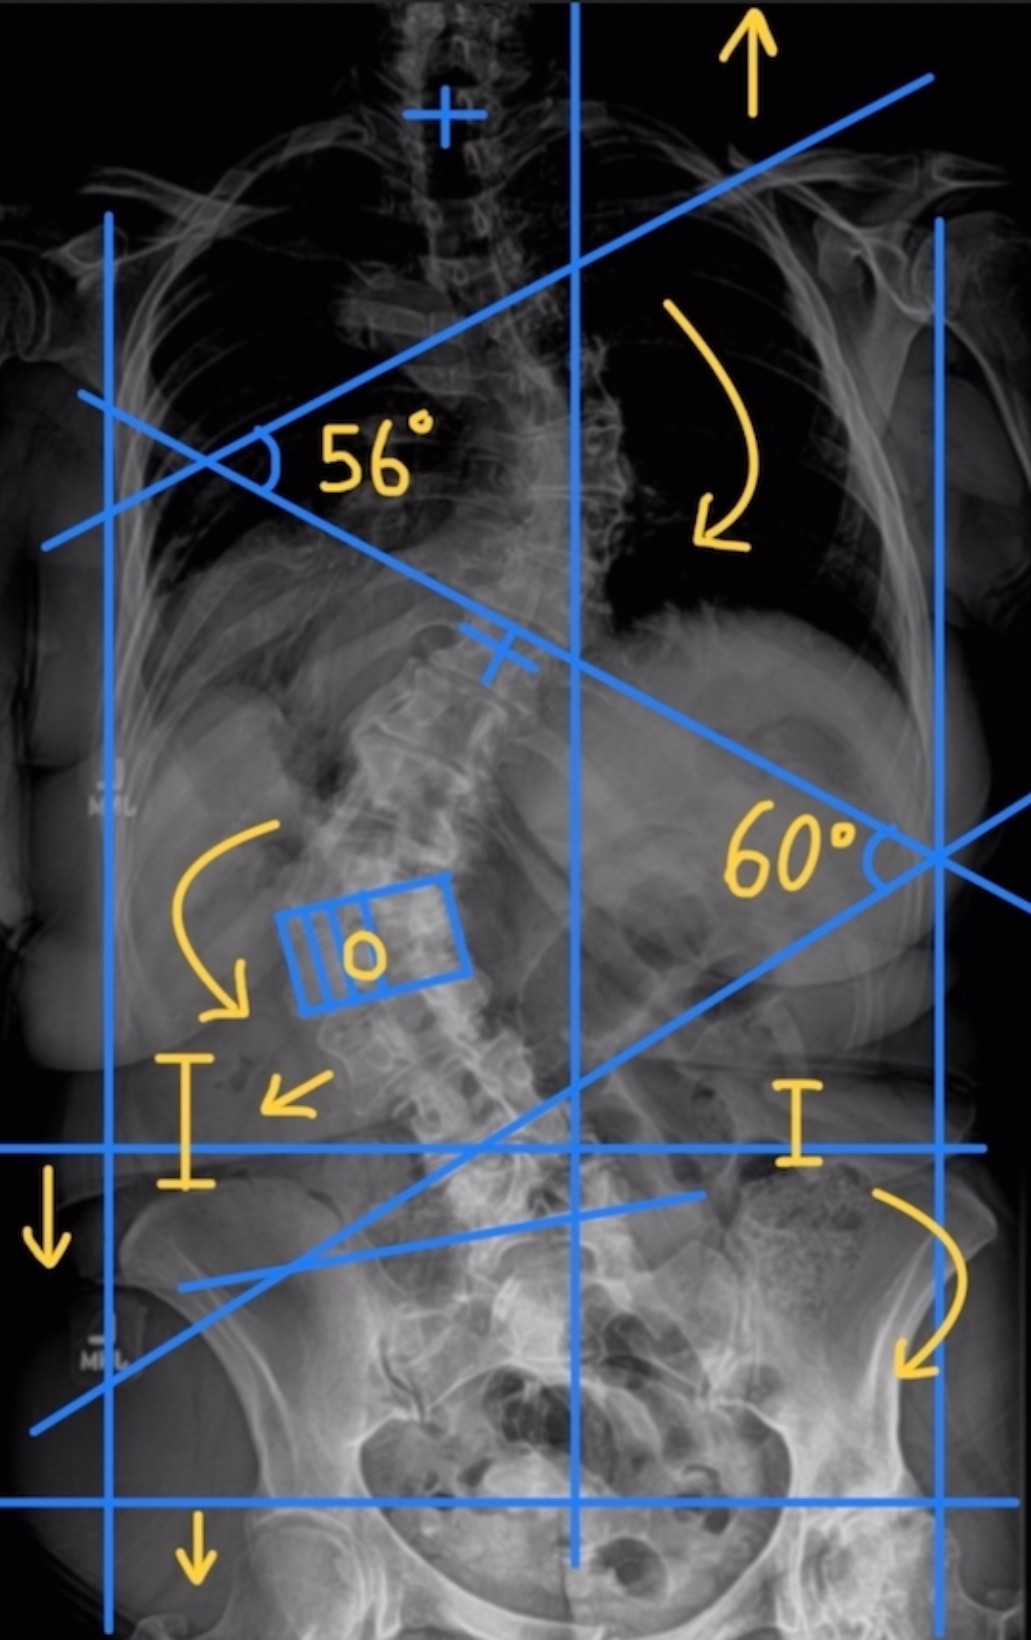

The paradigm for scoliosis treatment in the United States is shifting. 3-dimensional bracing and Schroth Exercise, which have been mainstays of scoliosis treatment in Europe for decades, are finally proliferating in the U.S. Schroth Therapy was only introduced in the U.S. in 2004, Rigo-Cheneau style bracing was introduced shortly afterwards in 2005, but establishing these practices as the standard of care has been a long road. For decades, including the 2000’s, and 2010’s, our treatment options for scoliosis have been “do nothing until the curve is big enough to brace”, “wear a brace”, and “spinal fusion surgery”, with NOTHING in between. Beginning around 2010, studies started popping up in the literature investigating the efficacy Schroth Therapy. Now, it is the most thoroughly studied non-operative scoliosis treatment method available. Many providers still don’t think of recommending physical therapy for scoliosis patients because for so long, it wasn’t even an option. Larger metro areas like New York, LA, and Seattle all have a dozen or so Schroth trained therapists now, but Phoenix has been behind the curve (as has the Southwest as a whole). Thankfully, more and more therapists are becoming certified in the Phoenix area, and Schroth Therapy is starting to trickle into smaller, previously desolate regions for scoliosis treatment. Providers of all types who want to stay up-to-date with best practices for scoliosis should familiarize themselves with the robust body of research, find Schroth trained therapists in their area, and offer physical therapy as an option to their patients.

Scottsdale Scoliosis & Spine Therapy is the largest provider of Schroth Therapy in Arizona. The Schroth Method is the gold standard globally for non-surgical intervention. It differs from traditional physical therapy in that each exercise is designed specifically to address a person’s individual curve. Stock photos cannot represent the detail, the intricacies, and the customization involved in a Schroth Exercise. I spend a lot of time doing education with patients so they understand WHY they are doing their exercises, not just aimlessly reading from a list. This ensures a more comprehensive understanding of your curve pattern, which is essential for autonomy with your scoliosis care. My goal for patients is for me to be the last provider they ever have to see about their scoliosis. I want my patient’s to have an understanding so thorough, so detailed, and so advanced, that they can avoid complications of their scoliosis in the future, and if complications are unavailable, they will understand how to address the problems by themselves.